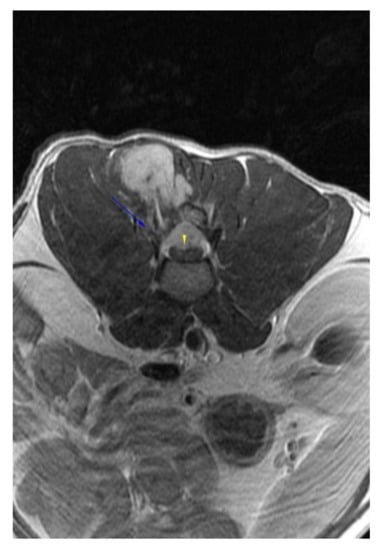

:1. Case Description

2. Materials and Methods

3. Results